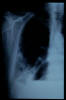

Paquipleuritis. Fractura costal.